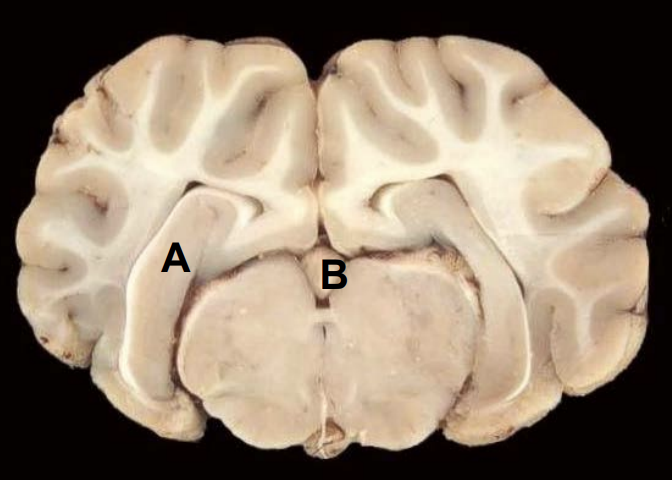

11

Hippocampus

12

Pineal gland